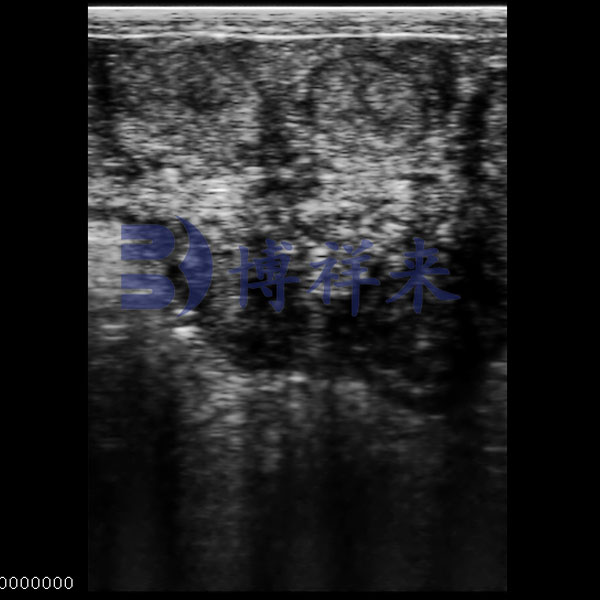

Ovarian Follicle Ultrasound

● Displays multiple follicle cavities of varied shapes.

● Layered echoes for structural recognition.

● Shows cavity distribution and size.

● For reproductive monitoring in livestock.